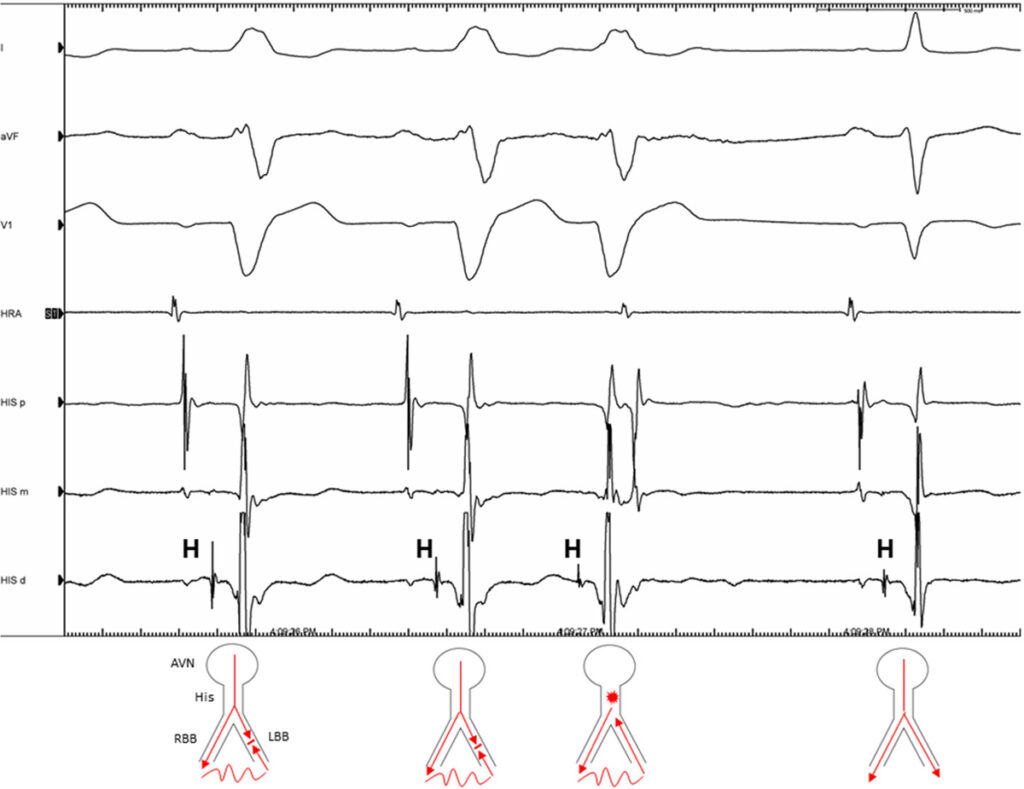

機能的脚ブロック

左脚の機能的ブロックの場合を考えると、まず左脚ブロックのため興奮は右脚を伝導します。右脚を伝導した興奮は心室中隔を越え、その間に不応期を脱した左脚へ逆行性に潜伏伝導します。これにより、次の上室性の興奮が伝導してきた時に左脚が不応期の状態なので興奮がブロックされます。この反復的な逆行性の潜伏伝導パターンにより、十分に早い期外収縮が発生するまで機能的左脚ブロックが持続します。

十分に早い心室期外収縮によって左脚への逆行性伝導が発生した場合、左脚の不応期の開始点は前倒しになり、次の洞結節からの興奮が伝導してくるまでに時間があるため、左脚の不応期が回復するのに十分な時間があります。また、脚の不応期は直前のRR間隔に大きく依存するため、期外収縮の連結期が短いほどRR間隔は短くなり、期外収縮後の左脚の不応期は短くなります。

そのため、次の興奮では両方の脚が伝導可能となり、narrow QRSで伝導します。このようなメカニズムにより、十分に早い心室性期外収縮やペーシング後のQRS波は機能的脚ブロックが解除されて正常化します。